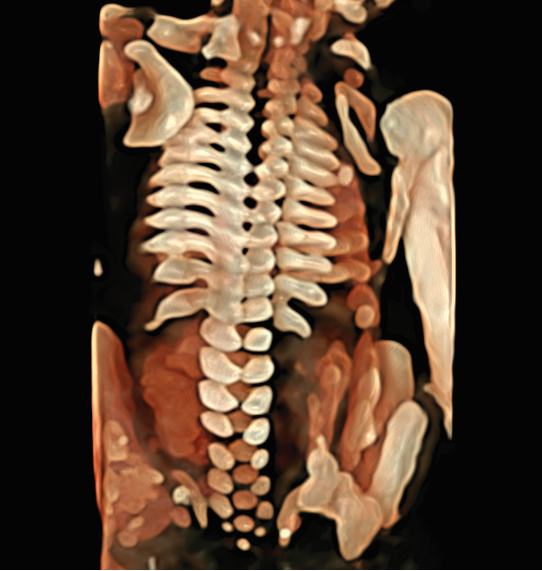

1、胎儿及胎儿附属器的异常检查更卓越

用于胎儿颜面部、 中枢系统及脊柱异常的显示, 通过细致的多切面成像分析胎儿的解剖结构及发育状况。

4、9大胎儿核心部位独立成像

E10独有的表面模式、血管模式、组织血管透明模式等智能诊断模式,对胎儿的体表、内脏、血管、骨骼等9大核心部位独立成像,全面弥补传统系统四维彩超在检测范畴及精准度的局限性。